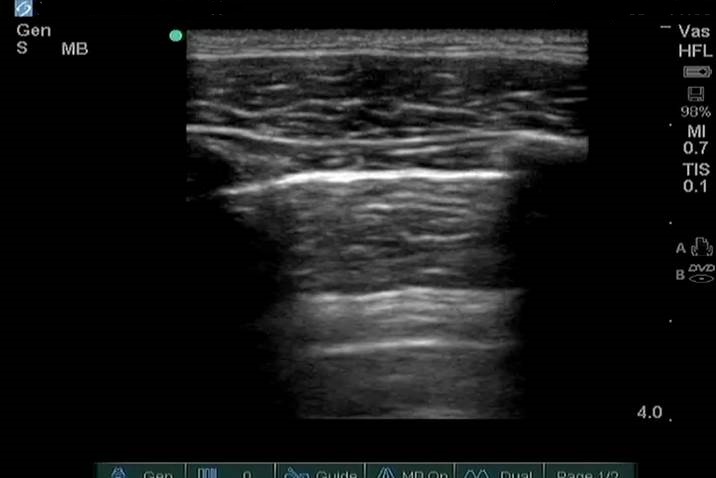

Lung No Lung Sliding Example Image